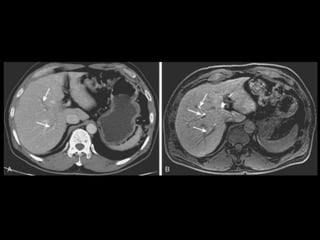

Técnicas de Imagem •US: Primeiro exame pedido ao: 1) dor no hipocondrio direito; 2) testes de função hepáticas anormais; 3) suspeita de malignidade. • TC: Tres fases – Arterial (10 a 20 segundos) – Fase venosa portal ( 30 segundos ) – Fase venosa hepática (60 segundos) • TC Portografia: Metastases.